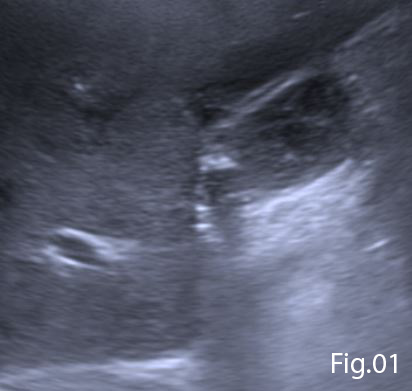

B-mode ultrasound demonstrated complicated gallstones with low level echogenic debris within the gallbladder. The gallbladder wall was thickened and ill-defined anteriorly (Figure 1). Within segment V of the liver, adjacent the anterior gallbladder wall was an ill-defined hypoechoic lesion containing complex fluid components, these findings were suggestive of a hepatic abscess. A second larger hepatic abscess was noted in segments V/VIII (Figure 2).